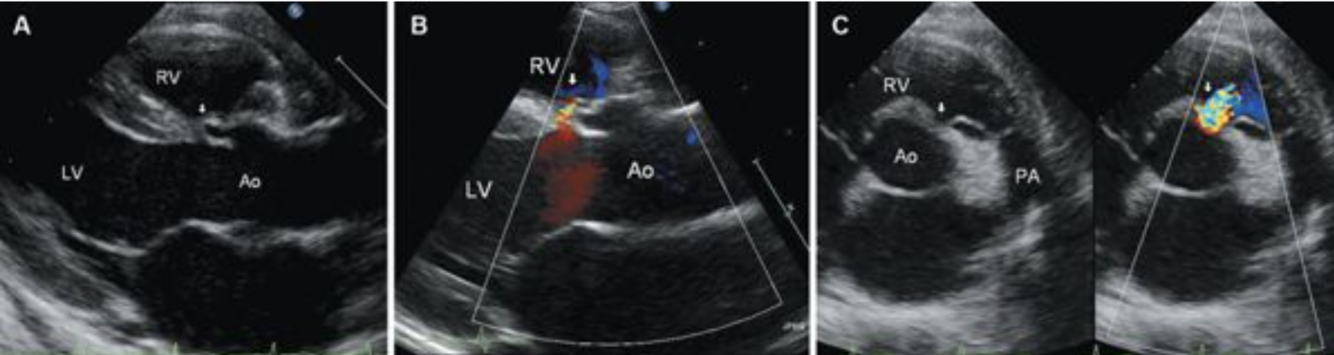

17

Q

What is this? Be Specific

A

Muscular VSD

18

What is this? (Be specific)

Inlet VSD